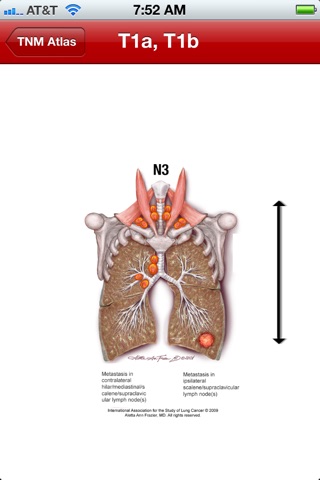

Presents IASLC-recommended changes for lung cancer staging in the UICC and AJCC 8th edition of TNM. Includes IASLC-original illustrations, beautifully rendered specifically for the iPad and smartphone media. Especially valuable to oncologists, surgeons, radiologists, scientists, and pathologists working in the field of thoracic oncology.